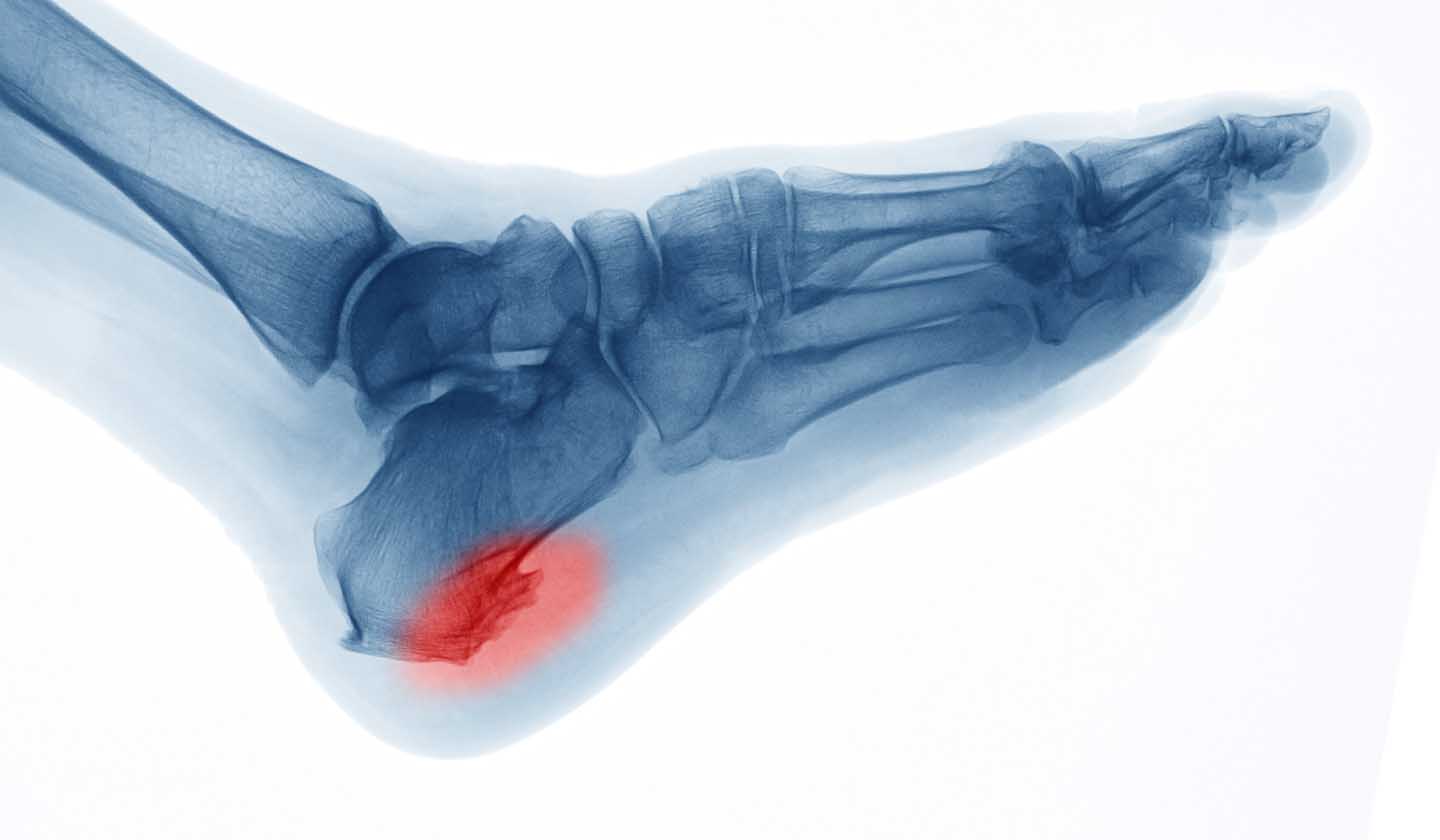

What is a heel spur?

It is a bony protuberance (which reflects an abnormal calcium deposit) that forms at the bottom of the calcaneus (heel bone), next to the insertion of the plantar fascia or in the posterior region of the calcaneus, next to the insertion area of the Achilles tendon.